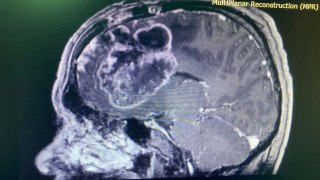

Фото управления здравоохранения Туркестанской области Казахстанские врачи спасли трёхмесячного ребёнка с кровоизлиянием в мозг Нейрохирурги детской больницы провели сложную операцию трёхмесячному ребёнку в Сарыагаше, передаёт TengriHealth.